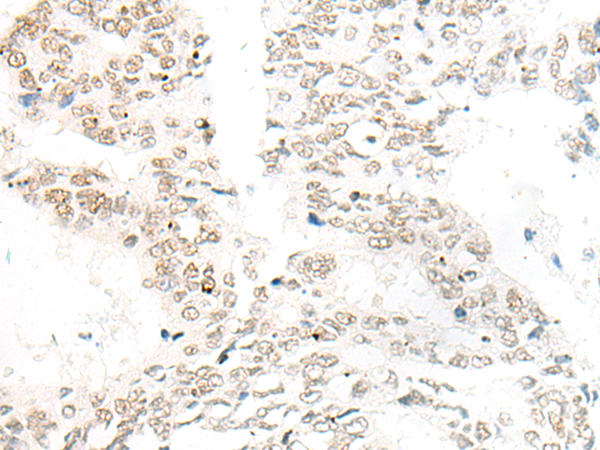

分类: 科研抗体货号: P06442别名: IL-34; C16orf77应用: WB,IHC反应种属: Human